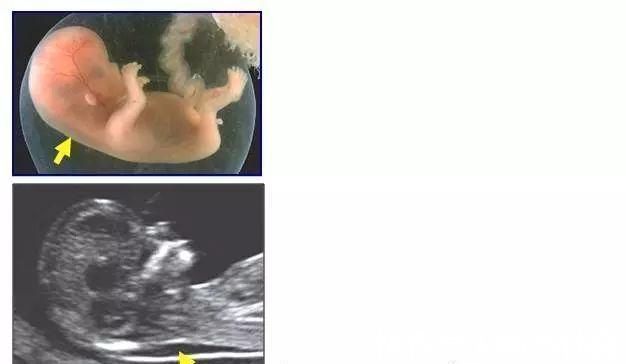

NT检查+唐氏筛查+DNA无创检查!——这是第一次通过检查胎儿颈后透明层来预判胎儿的健康度(是否有痴呆),这阶段也是最熬人的。

提示:颈后透明层正常范围是小于3mm,大于3mm的要格外注意了。